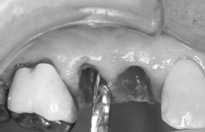

1週間後です。切開してないので歯肉の治りも早いです。 |

術後 |